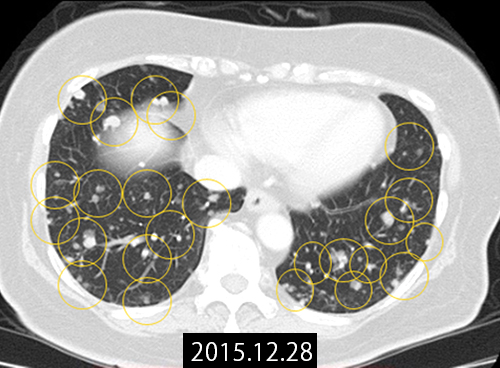

CT画像で見る治療経過

転移巣の治療経過

治療前のCT(図1)では左右両葉に多発肺転移を認めました。当初本人が化学療法を拒否されていたことから、不正性器出血を制御する目的で原発巣(子宮)のみに対し放射線治療を行う方針としました。放射線治療前に成分採血を行い、WT1樹状細胞ワクチンの作成を実施しました。

本症例では、原発巣への限定的な放射線治療と、規定量以下の化学療法、そしてWT1樹状細胞ワクチン療法を組み合わせる治療を行いました。このような治療の組み合わせと順序により、多発肺転移巣の縮小が確認されました(図2)。

図1:2015年12月 多発肺転移(黄丸部)